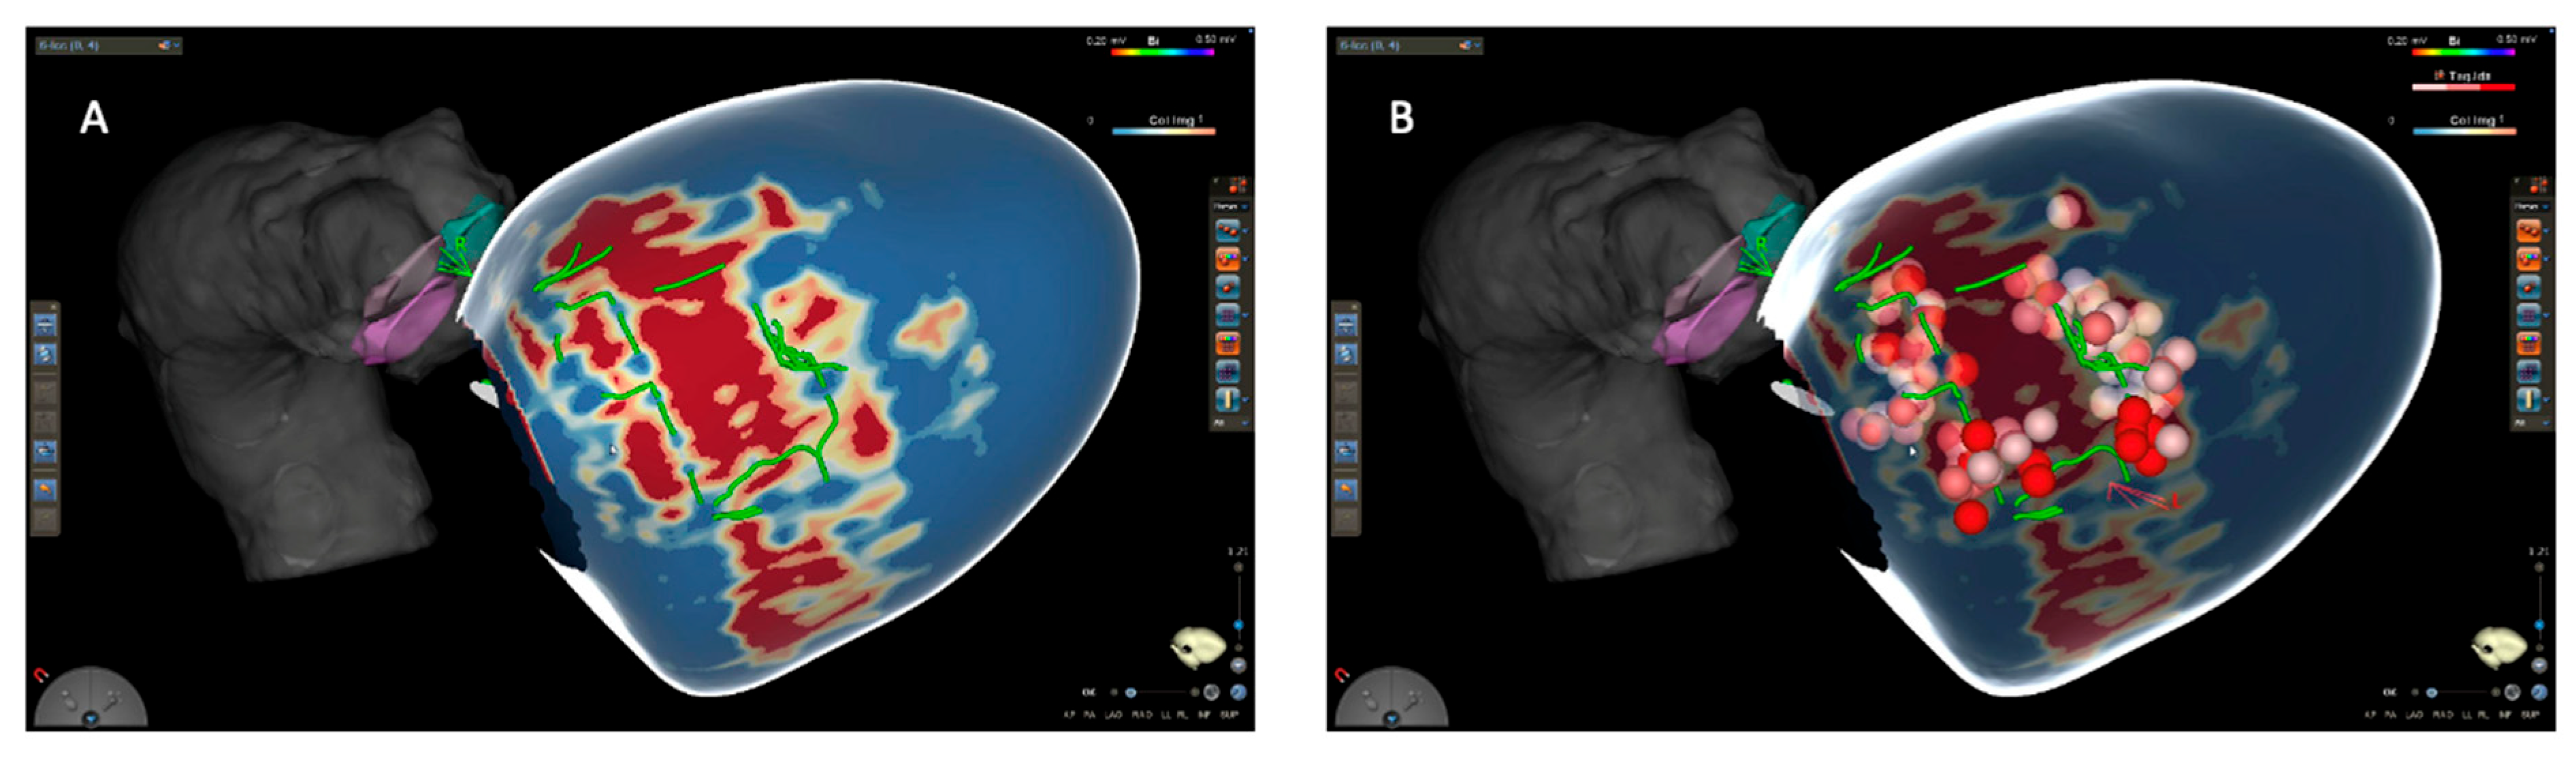

- Di Cori, A.; Pistelli, L.; Parollo, M.; Zaurino, N.; Segreti, L.; Zucchelli, G. Approaching Ventricular Tachycardia Ablation in 2024: An Update on Mapping and Ablation Strategies, Timing, and Future Directions. J Clin Med. 2024, 13, 5017. [Google Scholar] [CrossRef]

- Sanchez-Somonte, P.; Garre, P.; Vázquez-Calvo, S.; Quinto, L.; Borràs, R.; Prat, S.; et al. Scar conducting channel characterization to predict arrhythmogenicity during ventricular tachycardia ablation. EP Eur. 2023, 25, 989–999. [Google Scholar] [CrossRef]

- Andreu, D.; Penela, D.; Acosta, J.; Fernández-Armenta, J.; Perea, R.J.; Soto-Iglesias, D.; et al. Cardiac magnetic resonance–aided scar dechanneling: Influence on acute and long-term outcomes. Heart Rhythm. 2017, 14, 1121–1128. [Google Scholar] [CrossRef]

- Soto-Iglesias, D.; Penela, D.; Jáuregui, B.; Acosta, J.; Fernández-Armenta, J.; Linhart, M.; et al. Cardiac Magnetic Resonance-Guided Ventricular Tachycardia Substrate Ablation. JACC Clin Electrophysiol. 2020, 6, 436–447. [Google Scholar] [CrossRef] [PubMed]